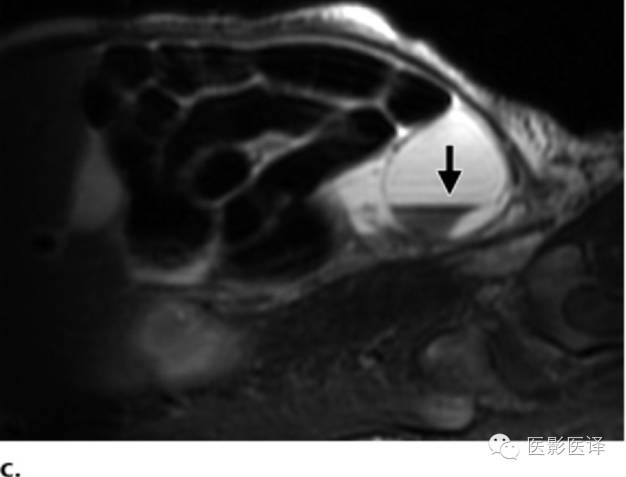

因母亲体型、胎儿位置或羊水过少而声学评价受限的病例,MR成像就很有帮助了(图8)。MR成像也可用于确认女性生殖器官和正常胃肠道及泌尿生殖道,这些是诊断胎儿卵巢囊肿所必须的。快速T2WIMR成像序列有助于显示解剖,TIWI MR成像显示胎粪为高信号,这能显示结肠走向并确认直肠。

图8MR图像可清晰显示胎儿解剖。(a)稳态进动MR图像矢状位显示一囊肿内伴多发分隔(黑箭),该囊肿位于肝脏下缘、肾脏(K)前缘。可见脐静脉(uv;白箭)进入肝左叶。(b,c)稳态进动MR图像横断位显示胎儿子宫(图b中箭头所示)位于膀胱(B)后方,提示女性内生殖器,阴唇(图c中箭头所示),提示女性外生殖器。证实了女性生殖器存在也就可以支持卵巢囊肿的诊断;若显示为男性生殖器则可以将卵巢囊肿从鉴别诊断中排除。